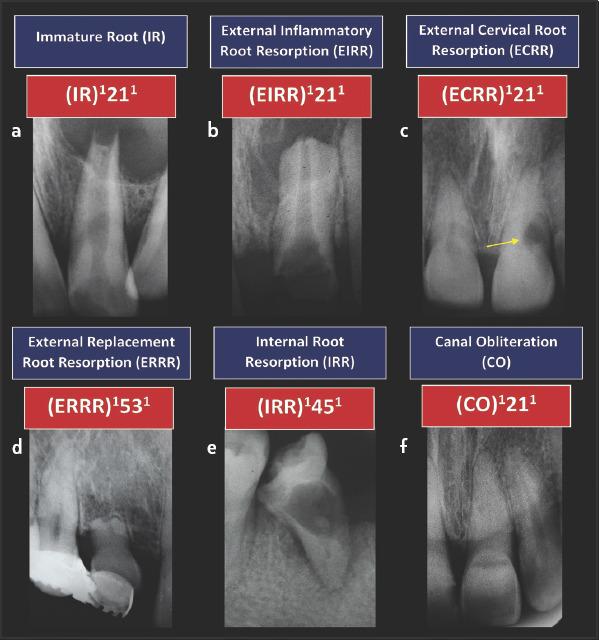

应用根管解剖分类新系统于临床实践:说明与详述。

Application of a new System for Classifying Root and Canal Anatomy in Clinical Practice - Explanation and Elaboration.

Adequate understanding and accurate characterization of normal and unusual root and canal morphology are essential requirements for successful root canal treatment. A new coding system for classifying root and canal morphology, accessory canals and anomalies has been introduced. In addition to technological advances related to experimental studies involving micro-computed tomography, the continuing clinical advances in magnification, illumination, imaging and intra-operative root canal treatment procedures have allowed clinicians to identify an increasingly wide range of anatomical variations in roots and canals in an attempt to achieve more predictable clinical outcomes. This review aims to provide a step-by-step explanation for the clinical application of the new coding system in dental practice, and to describe the anatomical variations in roots and canals for teeth scheduled for root canal treatment.

充分理解和准确描述正常和异常的牙根和根管形态是根管治疗成功的基本要求。引入了一种新的根管形态、副根管和异常分类编码系统。除了与涉及微计算机断层扫描的实验研究相关的技术进步外,放大、照明、成像和术中根管治疗程序的持续临床进展使临床医生能够识别越来越广泛的根和根管的解剖变异,试图实现更可预测的临床结果。本综述旨在为新编码系统在牙科实践中的临床应用提供逐步解释,并描述计划进行根管治疗的牙齿的牙根和根管的解剖变异。